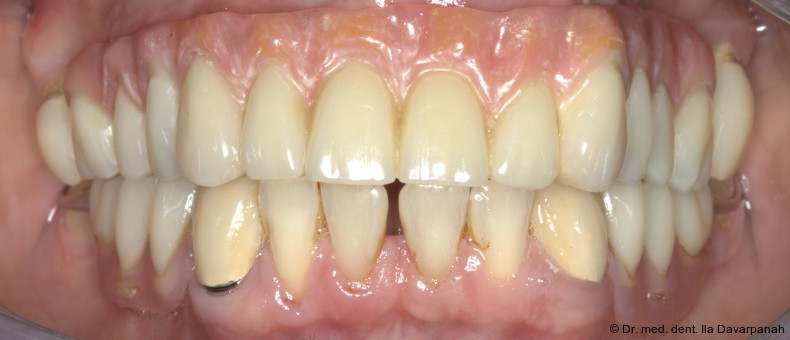

Die definitive Prothese konnte im dritten Behandlungstermin problemlos eingegliedert werden. Es waren lediglich minimale okklusale Anpassungen erforderlich (Abb. 20–24).